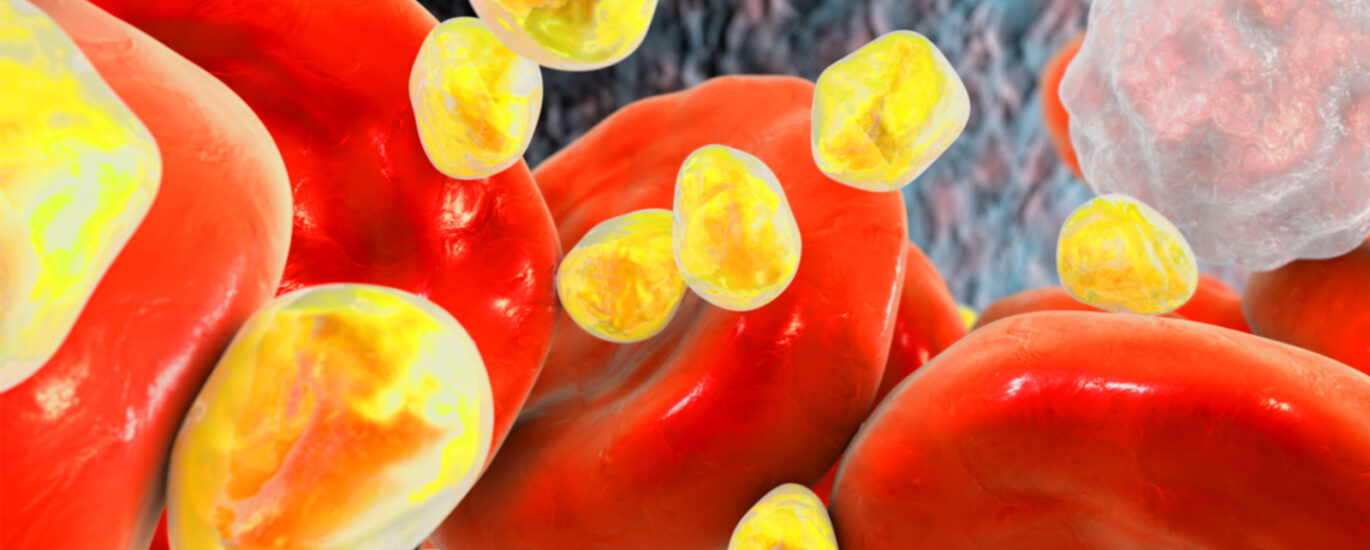

Heterozygous Familial Hypercholesterolemia, a condition characterized by elevated levels of cholesterol in the blood, poses a significant health risk by impeding blood flow and increasing the likelihood of heart attacks or strokes. The pressing need for effective management of this condition has fueled the surge in the global HEFH Management Market.